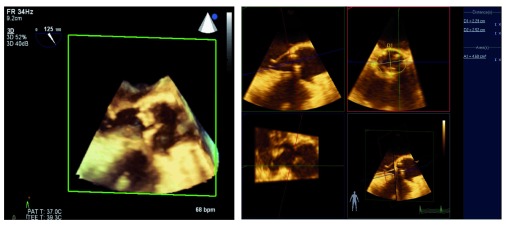

Figure 2. Three-dimensional assessment of the mitral valve has led to improved identification of pathology and guided repair.

The native mitral valve (left) shows an anterior leaflet cleft and a posterior leaflet prolapse. Surgical repair includes mitral annuloplasty ring and Alfieri stitch (right), resulting in two distinct inflow orifices. 3D, three-dimensional; bpm, beats per minute; PAT T, patient temperature; TEE T, transesophageal echocardiography temperature.

Figure 3. The three-dimensional view of the left ventricular outflow tract (left) allows precise measurement of the aortic valve annulus (right).

This technique is used to guide percutaneous aortic valve replacement and has been shown to be equivalent to computed tomography angiography for this purpose. 3D, three-dimensional; bpm, beats per minute; PAT T, patient temperature; TEE T, transesophageal echocardiography temperature.